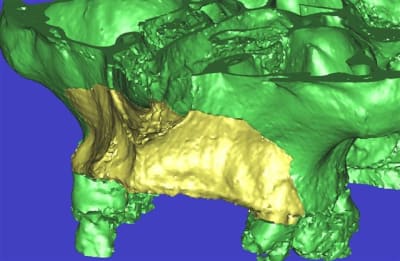

dar_3d1_iido9a.jpg

l'étude en partant des blocs standards

La première diapo est un essai pour justifier le concept (os non destiné à une utilisation greffe)

la deuxième est "tapée" dans une tête de femur de mauvais qualité (rejetée)

la troisième et suivante ce sont "les greffons" définitifs.

concept très prometteur. on obtient effectivement un contact intime du greffon avec le site receveur.